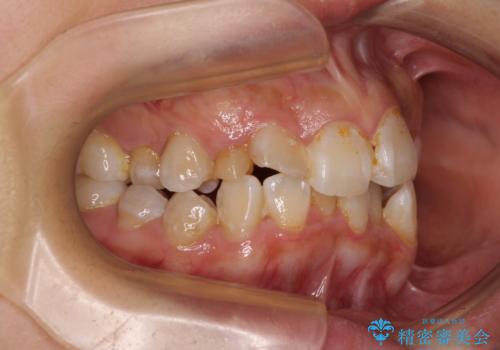

- 上下前歯のデコボコを気にして来院された患者様です。

上顎は両側の犬歯が骨内に埋伏しており、乳歯が残存している状態でした。

歯肉内に埋もれている場合には牽引することも可能ですが、両歯ともに骨内に完全に埋もれていたため、牽引することは不可能と判断しました。

口元の突出感があるわけではなく、叢生の程度もシビアではありませんでしたが、顎骨が小さく、左右ともに最後臼歯が歯肉に埋もれているため、下顎は左右第二小臼歯を抜歯することとしました。

上顎は左右ともに残存している乳歯を抜歯し、上下歯列を整えることとしました。